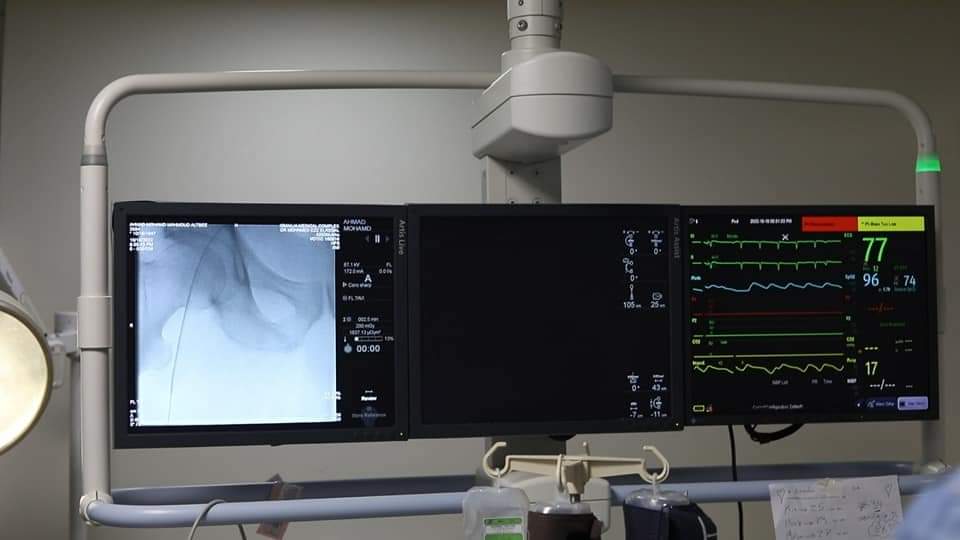

نجح فريق طبي مكون من 13 طبيبا وفنيا بقسم القلب بمجمع الإسماعيلية الطبي، في إجراء جراحة لزراعة صمام للقلب عن طريق الشريان الفخذي بالقسطرة بتقنية TAVI، دون الإحتياج إلى تدخل جراحي.

حيث تم إجراء الجراحة لمسن يبلغ يعاني من الأمراض المزمنة يبلغ من العمر 77 عاما، وكان يعانى من ضيق حرج فى الصمام الأورطي نتج عنه ضعف شديد بعضلة القلب، الأمر الذى يُعد التدخل الجراحي التقليدي فيه عالى الخطورة، لذلك كان الاختيار الأمثل والأفضل للحفاظ على حياة المريض هو تغيير الصمام عن طريق استخدام القسطرة القلبية.

وتكمن خطورة حالة المريض كونه مصاب بسدة رئوية، حيث كان متكرر الإصابة بالإرتشاح الرئوي، وذلك نتيجة لضعف عضلة القلب مما استلزم التدخل دوائيًا لتقليل مضاعفات فشل عضلة القلب لديه، قبل إجراء العملية.

ويضم الفريق الطبي أمهر أطباء القساطر القلبية والذي قام بزراعة الصمام الأورطى بإستخدام تقنية TAVI حيث ترأسهم الاستاذ الدكتور طارق رشيد، أستاذ القلب، واستشاريي القلب والقسطرة، والدكتور محمد عز الرجال، والدكتور محمد سليمان، والدكتور شادى عقل، والدكتور وسام الصاوي "أخصائيي القلب والقسطرة"، وبمشاركة استشاريين التخدير الدكتورة شيماء دهشان، الدكتور أحمد أيمن، وبمعاونة فريق التمريض المتميز المكون من «مصطفى غريب، محمد جمال، إسلام طلعت» وفنيوا الأشعة « هبة احمد، محمد حسام، أحمد عبد الغني».